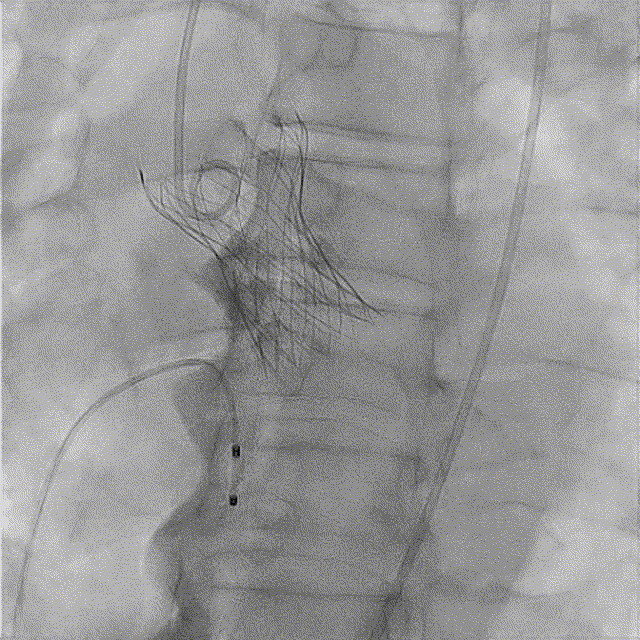

全麻后超声引导下建立入路,左侧股动脉置入TaurusNavi 20F血管鞘。跨瓣后左室放置Lunderquist导丝,使用TaurusAtlas 20mm球囊预扩,球囊无明显位移,有轻微腰征、无漏。输送系统预备同侧Snare从右股动脉送入,安全顺利通过主动脉弓。瓣膜在双窦展开位约瓣上2mm位初始定位释放,工作位造影多角度评估后予以释放(一次定位释放,未采用多次回收功能)。超声下显示瓣膜偏椭圆,之后使用TaurusAtlas 22mm球囊后扩,支架形态改善明显,导管测压由术前的70mmHg即刻下降至1mmHg,术后即刻超声心动图评估显示瓣膜位置良好,微量瓣周漏,血流动力学指标理想。

最终造影

超声影像

血流动力学改善,瓣膜形态良好。